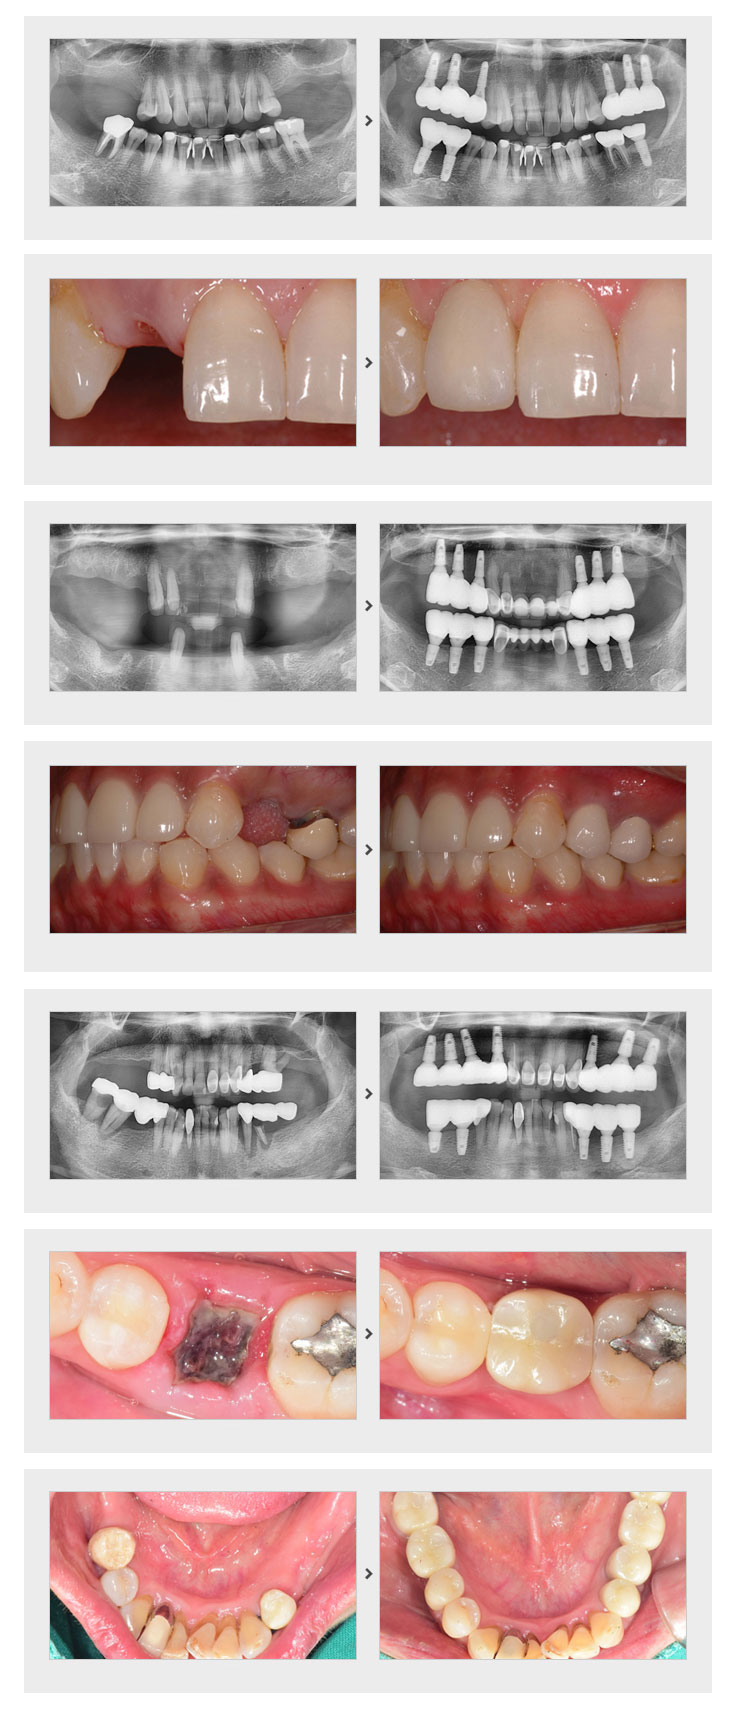

저희 의원은 환자 동의를 얻은 사진만 기재됩니다.